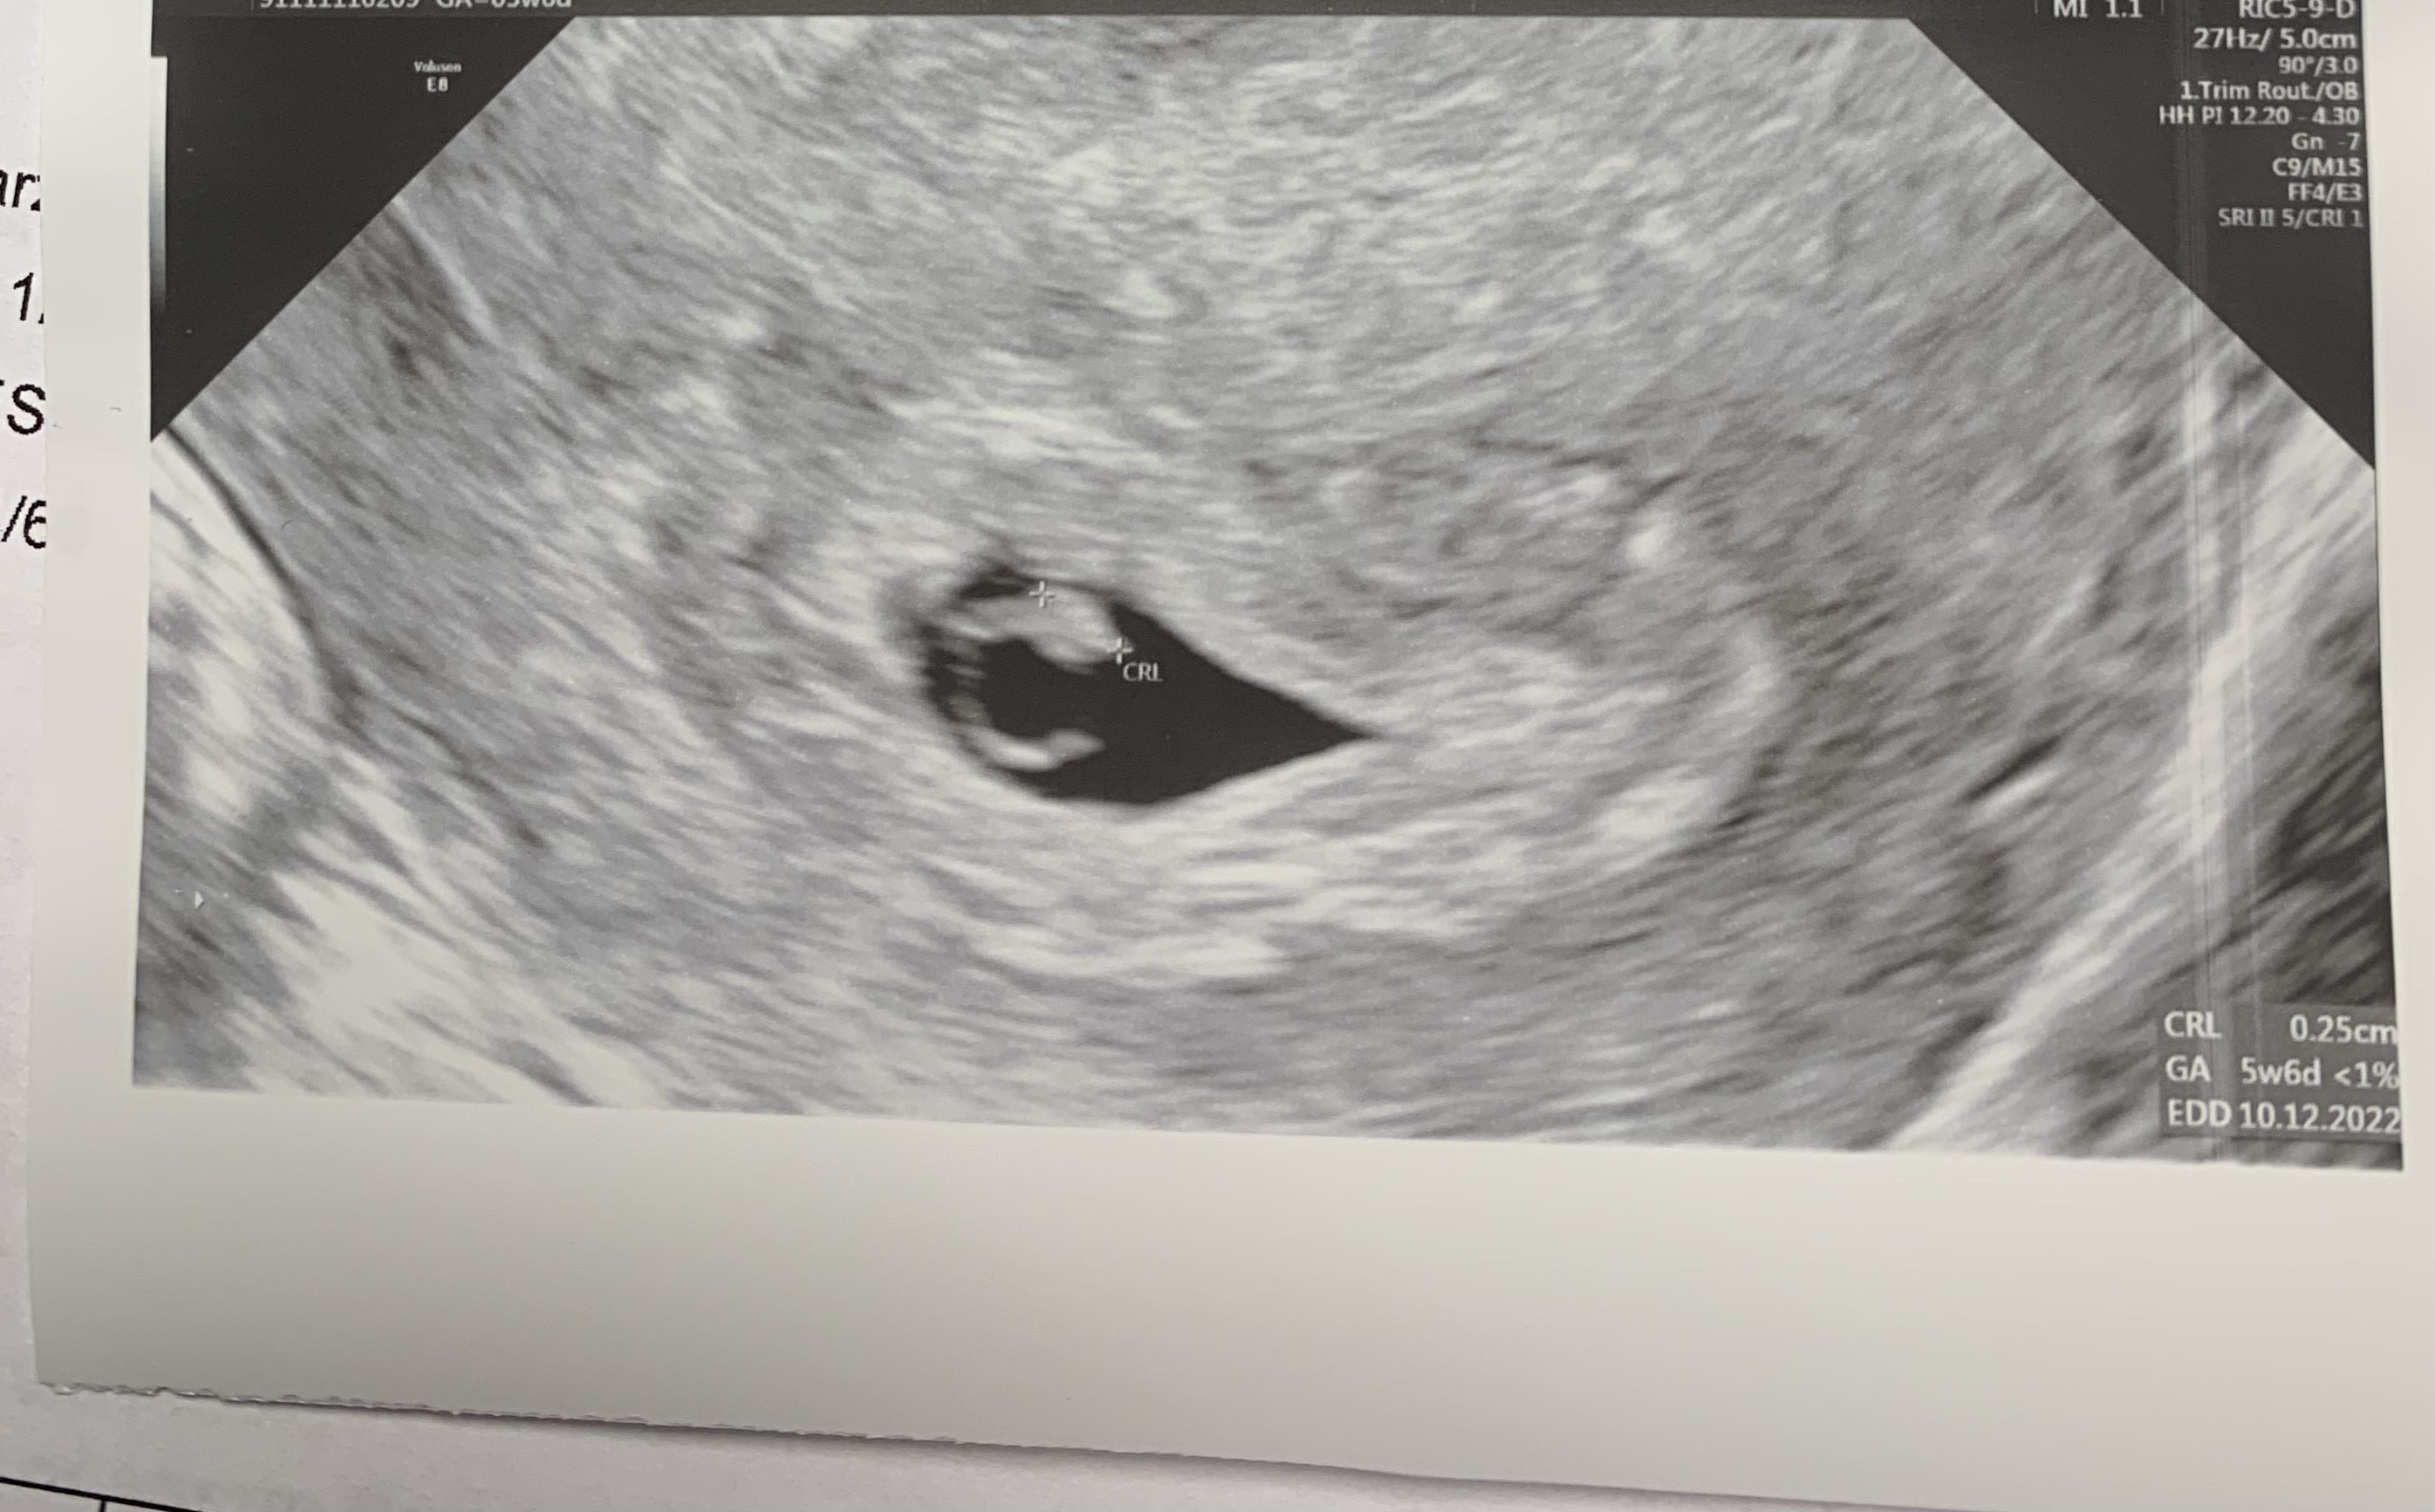

Pani Doktor powiedziala ze troche maly i splaszczony pecherzyk wiec zeby powstrzymywac jeszcze emocje. Jestem juz po poronieniu i ciazy pozamacicznej i ciezko powstrzymac.

Jest zarodek bije serce. Zaraz wrzuce foto Wam i wymiary.

Tutaj zdjęcja

Załączniki

• C3A7A489-C3EE-49EA-A308-D497768FE791.jpeg

C3A7A489-C3EE-49EA-A308-D497768FE791.jpeg

669,8 KB · Wyświetleń: 111